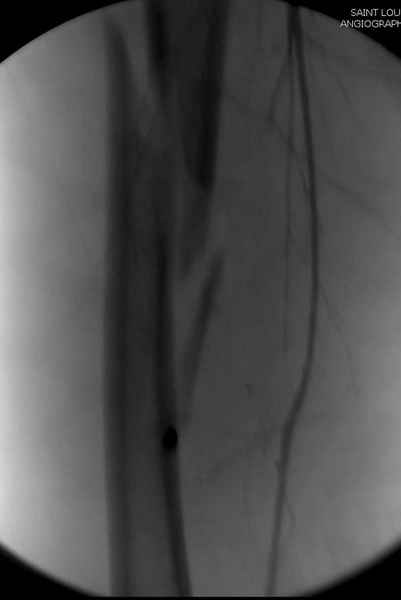

Как раз недавно у меня был примерный случай: больному 36 лет, поступил ночью, травма в результате мотоциклетной аварии, кроме чрезвертельного и спирального перелома левого бедра имеется переломы костей предплечья с этой же стороны. Скелетное вытяжение, а на следующий день больной про оперирован на ортопедическом столе с дистракцией. Чтобы не расколоть чрезвертельный перелом провели временную спицу ближе к переднему кортексу, из малого разреза костодержатель для репозиции, а фиксацию провели антиградным штифтом. Этапы операции на снимках.

Джолдас Кульджанов